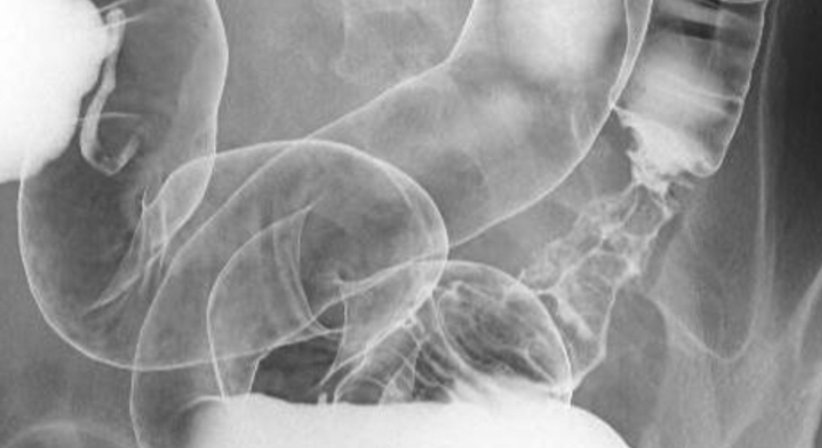

Im Rahmen von Röntgenuntersuchungen können durch die Verabreichung spezieller Kontrastmittel Innere Organe untersucht werden.

Für die Untersuchungen des Magens wird Kontrastmittel getrunken, für den Dickdarm wird ein Kontrasmitteleinlauf vorgenommen.